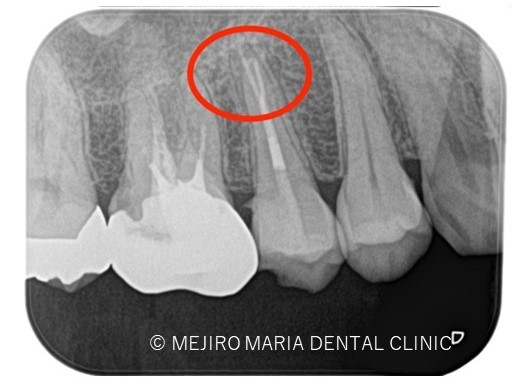

診査の結果、右上5番の歯髄には歯髄生活反応は確認できず、歯髄壊死が起因となる根尖性歯周炎と診断しました。術前のレントゲン診査により、根尖が2つに分岐していることを確認できます。

*赤丸で示しているところは、根が分岐している箇所を示す